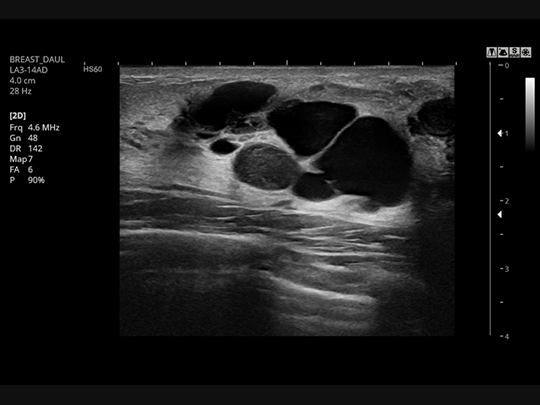

Linear array transducers

LA3-14AD

- Application: abdomen, musculoskeletal, small parts, vascular

S-Vision™ Imaging Engine

S-Vision™ imaging engine effectively removes noise artifacts resulting in clear, detailed resolution and tissue uniformity.

S-Harmonic™

This new harmonic technology provides greater image uniformity from near to far field while reducing signal noise.